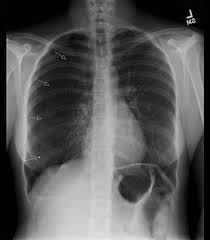

Pneumothorax - Pneumothorax : Doctors treat a pneumothorax or collapsed lung depending upon the cause.. Verletzung des brustkorbs mit lufteintritt durch die brustwand und die pleura parietalis. In tension pneumothorax, patients are distressed with rapid laboured respirations, cyanosis, profuse diaphoresis, and tachycardia. Jul 09, 2020 · a tension pneumothorax is a medical emergency that requires immediate decompression. Nov 08, 2017 · primary spontaneous pneumothorax: This website is designed primarily as an educational resource. Luftaustritt aus der lunge durch die pleura visceralis. A pneumothorax can develop into a collapsed lung. Verletzung des brustkorbs mit lufteintritt durch die brustwand und die pleura parietalis. A pneumothorax can be caused by: This air pushes on the outside of your lung and makes it collapse. Bilateral Tension Pneumothorax Is A Prompt Chest X Ray Useful Resuscitation Bilateral Tension Pneumothorax Is A Prompt Chest X Ray Useful Resuscitation from els-jbs-prod-cdn.jbs.elsevierhealth.com